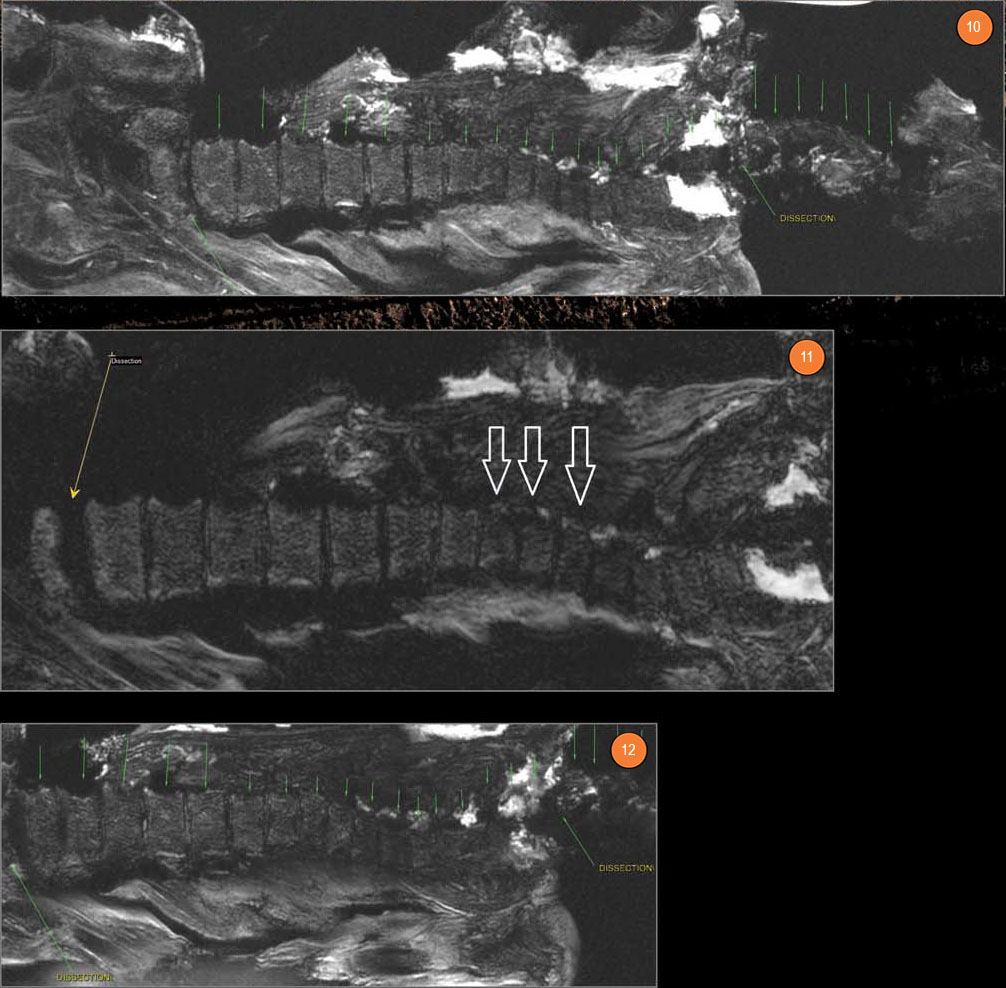

Рис. 10. Позвоночный столб мумии: в шейном отделе позвоночника 7 позвонков, в грудном — 12, а в поясничном — 5. Серия вертикальных зеленых стрелок показывает уровни по позвоночнику. Dissection — уровень артифициального рассечения на уровне шейно-грудного перехода. Сразу ниже него видны три грудных позвонка (Th1, 2, 3), деформированные и дающие сниженный МР-сигнал (по сравнению с нижележащими позвонками). Вокруг этих позвонков — отечные клетчаточные пространства (с высоким МР-сигналом). Второе рассечение без обозначения — на уровне крестцово-поясничного перехода (между крестцом и позвонком L5). Рис. 11. Компрессионные переломы тел позвонков Th8, 9, 10 (показаны полыми стрелками). Dissection — уровень артифициального рассечения на уровне крестцово-поясничного перехода (между крестцом и позвонком L5 — показано тонкой стрелкой). Рис. 12. Формирующиеся грыжи Шморля в телах позвонков Th8, 9, 10, 11, 12. Dissection — уровни артифициальных рассечений на уровне шейно-грудного и крестцово-поясничного переходов

В грудном отделе позвоночник сглажен (вероятно, посмертно), имеются прижизненные деформации тел позвонков как последствия компрессионных переломов, грыжи Шморля в различных фазах формирования, сподилезные разрастания и зафораменальные протрузии межпозвонковых дисков, особенно в нижней половине грудного отдела и в поясничном отделе позвоночника. Эти прижизненные изменения носят микротравматический и дистрофический характер, что контрастирует с молодым возрастом женщины.

В телах позвонков Th1, Th2 и Th3 выявляется значительное снижение МР-сигнала и деформация наружных контуров, что может указывать на прижизненное патологическое поражение губчатой костной ткани этих элементов, вероятно — метастатическим онкопроцессом, тем более что они «окружены» с обеих сторон паравертебральной клетчаткой с проявлениями резкой отечности.